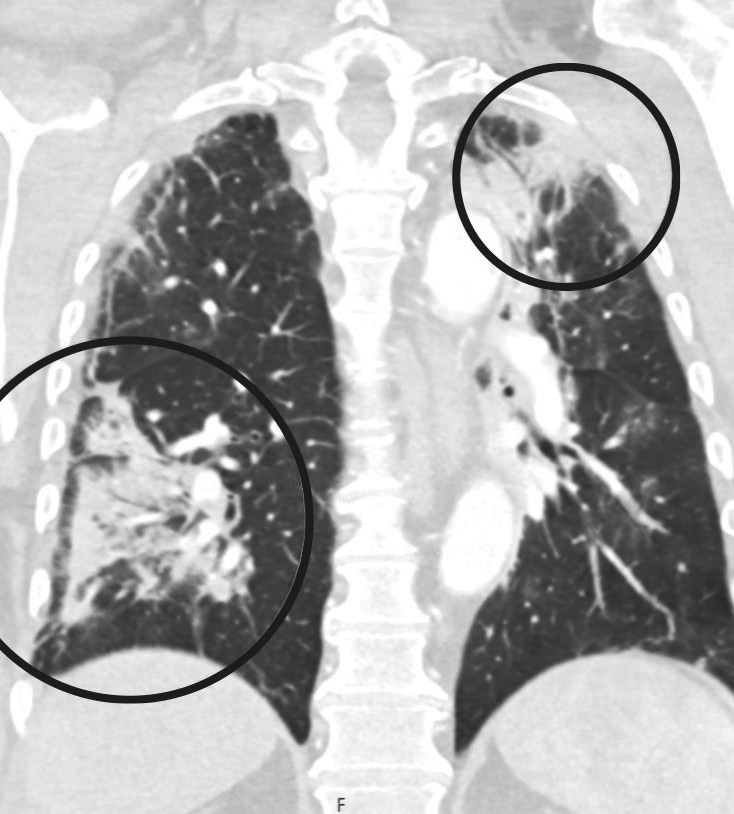

PCR-test for covid-19 ved innkomst var negativ, og pasienten hadde ingen respiratoriske symptomer. CT-angiografi viste manglende kontrastfylling fra begge aa. poplitea i kneleddsspalten (figur 1). Han hadde også okklusjoner distalt, men stedvis kontrastfylling av leggarterier, forenlig med tromboser i begge underekstremiteter. Pasienten fikk 5 000 IE dalteparin og ble deretter overflyttet til et regionssykehus.

Postoperativt var det tilbakegang av alle symptomer i bena, men pasientens oksygenmetning var påfallende lav med SpO2 på 94,5 % (referanseområde > 99 %). Blodgass tatt mens pasienten fikk 3 L O2 via nesekateter viste pH 7,47 (7,36−7,44), pCO2 4,5 kPa (4,5−6,1) og pO2 8,9 kPa (> 9,6). Det ble utført CT toraks-angiografi, som viste flere lungeembolier i begge underlapper samt mattglassforandringer typiske for gjennomgått covid-19-pneumoni (figur 2). I tillegg så man en 7 mm stor pendulerende trombe distalt i aortabuen (figur 3). Dalteparin ble økt til 10 000 IE × 2, og pasienten fikk ikke-invasiv respirasjonsstøtte på intensivavdeling.